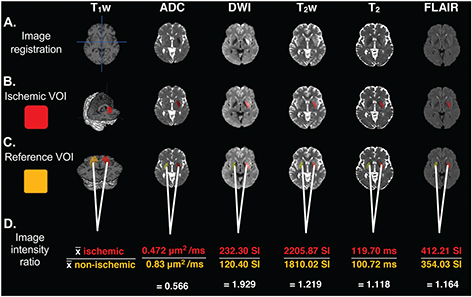

To quantify the subtle changes in T2 relaxation due to ischemia, both user-dependent and user-independent techniques have been devised in preclinical settings (20, 23, 24, 26, 27) and applied to MRI data of hyperacute ischemic stroke patients (21, 2831). The user-dependent mirror reference method is based on the principle that the T2 values in the non-ischemic hemisphere indicate pre-ischemic T2 values. The mirror reference method involves identifying the ischemic region using DWI or ADC images to create an ischemic volume of interest (VOI) (Figure 2). The ischemic VOI is then flipped across the midline to define the contralateral non-ischemic ‘mirror reference’ and loaded onto the T2-based image (Figure 2C). The change in T2 due to ischemia can be approximated by calculating: (a) the difference in the average values in both VOIs in milliseconds (26, 30), (b) the absolute percentage change (23, 24, 27) (Figure 1A and B), or (c) by calculating the ischemic vs. non-ischemic intensity ratio (29, 31, 32) (Figure 2D). The mirror reference method has reproducible T2 changes in rat stroke models (23, 26, 27) and hyperacute ischemic stroke patients (2831). It, therefore, has been proposed as a potential stroke timer, which could be used to stratify patients with unknown onset time to treatment (23, 24, 2632).

Figure 2. A mirror reference approach for quantifying changes in MRI measures in stroke. A. Images are registered to the T1 weighted image in MNI coordinate frame to correct anatomical alignment. B. ADC and absolute T2 limits are used to define the ischemic VOI. C. The mirror reference VOI is defined by reflecting the ischemic VOI across the midline, applying ADC and T2 limits and manually editing if necessary. D. The change in MR signal due to ischemia (image intensity ratio) is calculated by dividing the average of the ischemic VOI by the average of the non-ischemic VOI. Values are μms2/ms for ADC, signal intensities are an arbitrary scale for weighted images, and in ms for absolute T2 relaxation time maps. Images are from an acute ischemic stroke patient, scanned 6 hours and 49 minutes after symptom onset; with permission from (29) and (43).